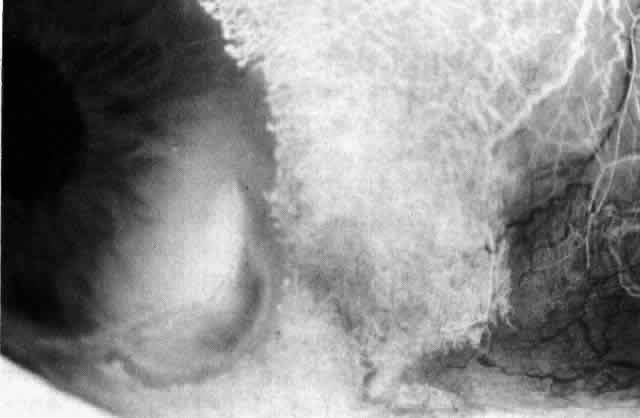

not be performed. Scleritis usually affects the anterior segment of the eye, possibly because

this is the area with the best blood supply, but with sluggish flow

through the vessels (Fig. 19). The sclera is thickened and roughened in the affected area, which appears

to be sharply demarcated from the rest of the sclera. However, tissue

obtained at surgery during the course of grafting of areas adjacent

to necrotic tissue shows marked pathologic changes.20,21 The area of affected sclera may be swollen, excavated, or frankly ulcerated

with undermined edges covered with a thin layer of fibrous tissue. However, spontaneous

perforation is extremely unusual and, where seen

in pathologic specimens, has usually occurred at the time of removal

of the eye. A posterior scleritis often occurs as an extension of anterior

disease; but, as in Figure 20, most of the inflammation (in some cases all of the inflammation) is in

can be mistaken for malignant melanoma.  Fig. 19. Anterior necrotizing scleritis. The eye was removed because of loss of

vision and intractable pain. No form of steroid was given to this patient

because of a severe Pseudomonas infection of the chest. (Courtesy of Professor N. Ashton) Fig. 19. Anterior necrotizing scleritis. The eye was removed because of loss of

vision and intractable pain. No form of steroid was given to this patient

because of a severe Pseudomonas infection of the chest. (Courtesy of Professor N. Ashton)

|